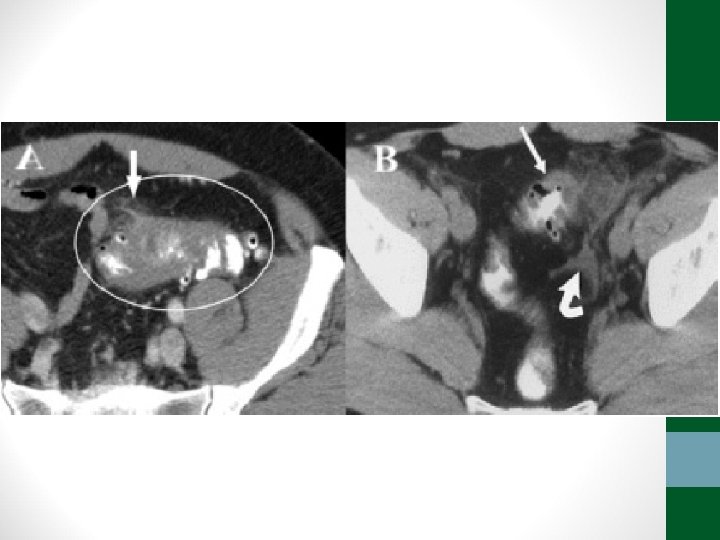

Exames de Imagem • Abdome Agudo Vascular: • Radiografia simples de abdome: decúbito, ortostase e cúpulas diafragmáticas • USG abdome não ajuda! • TC Abdome com contraste EV e VO – angio. TC (fase arterial e portal) é o melhor exame

Abdome Agudo Vascular • 50 a 70% de mortalidade • Causa relevante de óbito em pacientes internados em UTI • Diagnóstico e tratamento precoces (até 6 h do início da dor) aumentam a sobrevida • Requer alto índice de suspeição, pois os sintomas são inespecíficos no início do quadro • Pode ser confundido com quadro de obstrução intestinal

Abdome Agudo Vascular • Etilogia: • Isquemia arterial oclusiva • Embolia (50%) • Trombose (20%) • Isquemia arterial não-oclusiva (25%) • Trombose venosa (5%)

Trombose arterial Embolia arterial Isquemia arterial não-oclusiva Trombose venosa Quadro clínico Dor abdominal difusa intensa, sem irritação peritoneal. Antecedente angina mesentérica Dor abdominal difusa e intensa, sem irritação peritoneal Paciente crítico com ditensão abdominal, febre, leucocitose, sangramento digestivo Dor e distensão abdominal mais insidiosa. Sangramento digestivo comum Intestino acometido Todo delgado e cólon direito Poupa intestino delgado proximal Variável Poupa cólon Doenças associadas DAOC, AVC, FA, ICC dilatada, operação vascular IAM, AA, AVC, prévia procedimento endovascular ICC grave, uso DVA, Trombofilias, PV, PO cirurgia cardíaca, cirrose hepática, cocaína, ergot neoplasias, ACOH Tratamento Revascularização da AMS ou fibrinólise. Se necrose: ressecção e reabordagens Infusão intra-arterial de vasodilatadores (papaverina). Se necrose: ressecção e reabordagens Embolectomia da AMS ou fibrinólise. Se necrose: ressecção e reabordagens Anticoagulação plena. Se necrose: ressecção e reabordagens